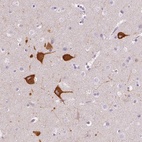

Immunohistochemical staining of human cerebral cortex shows cytoplasmic positivity in neuronal cells.